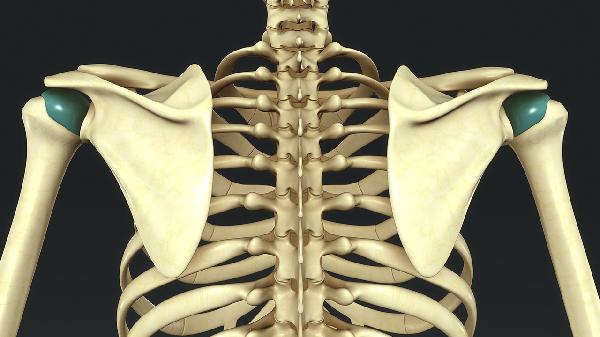

胸廓出口综合征可能由先天性骨骼异常、颈部或肩部外伤、不良姿势、肌肉肥大、肿瘤压迫等因素引起。胸廓出口综合征是锁骨与第一肋骨之间的神经血管束受压导致的疾病,主要表现为上肢疼痛、麻木、无力等症状。

颈肋或第一肋骨发育异常可能直接压迫臂丛神经或锁骨下血管。颈肋是颈椎额外生长的肋骨样结构,约0.5%-1%人群存在此变异。这类患者通常在20-40岁出现症状,可能伴随手部肌肉萎缩。治疗需通过手术切除异常骨结构,常用术式包括经腋路第一肋骨切除术。